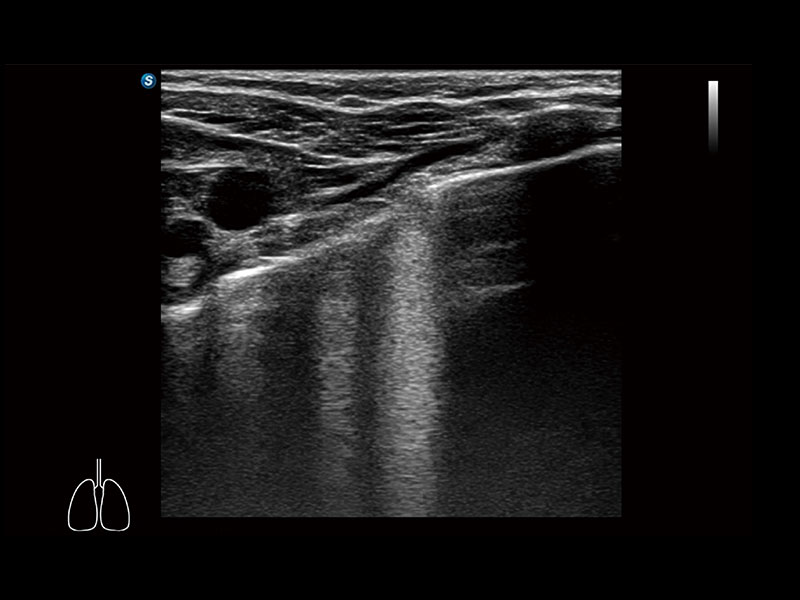

作为开立医疗全新打造的高端床旁笔记本超声,E11不仅具备卓越的图像质量,同时搭载全面高效的自动测量工具,助力医生实现更快速、更精准的床旁诊断。

E11搭载了丰富的自动化测量工具,以及专为POC科室定制的高级功能;同时配备了为急诊医师量身打造的 SonoFast急重症超声流程,以帮助临床医生最大限度的提升工作效率